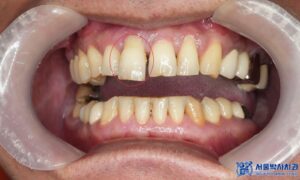

치료 마무리 후 사진입니다.

치료 후 환자분께서 거울을 보시면서

이렇게 자연스럽게 치료될 줄 몰랐다고 하시며,

임플란트 해야 하는 줄 알았는데 자연치아를

살릴 수 있어서 너무 만족한다고 좋아하셨습니다.